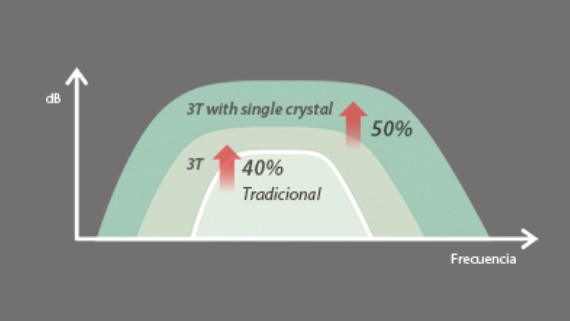

Transductores